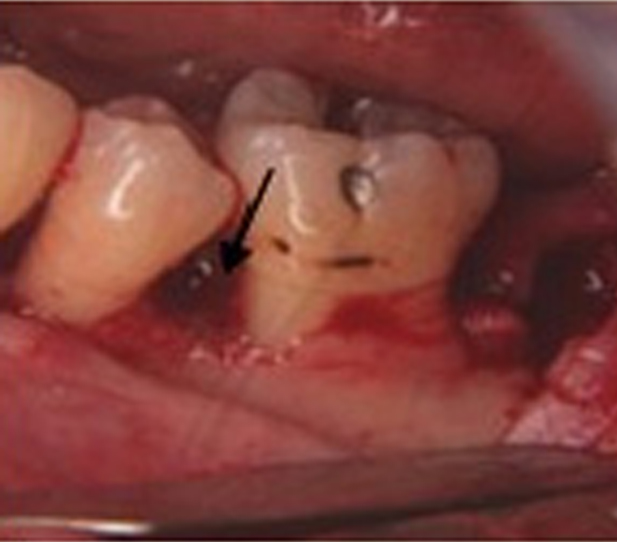

This method, which is a deep mass removal and non-surgical method, is performed under local anesthesia. Hard mass and sediment (tartar) are removed from the areas above and below the gum line (scaling).

Also, any hard stains created on the teeth’ deep areas are cleaned. Deep cleaning removes bacteria, and the clean surface of the gums is reattached to the teeth.

The gum is pulled up during this treatment, and the plaque is removed. In some cases, the irregular surfaces of the damaged bone are smoothed.